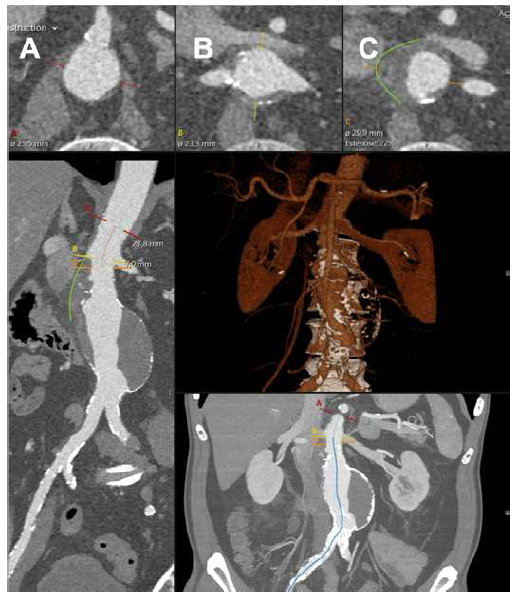

Given the patient’s sudden abdominal complaints and a previously identified AAA, a computed tomography angiography (CTA) was performed. The CTA revealed a 60 mm juxta-renal abdominal aortic aneurysm with signs of instability, characterized by parietal contour discontinuity at the proximal neck without active contrast extravasation (Figure 1).

The top panels show the superior mesenteric artery (panel A), renal arteries (panel B), and aneurysm origins (panel C). The green lines outline the signs of instability in the neck.